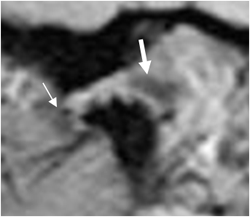

Fig 7. Disco luxado.

RM GE sagital oblicuo con boca cerrada. Desplazamiento anterior del disco. Banda anterior. (Flecha delgada).